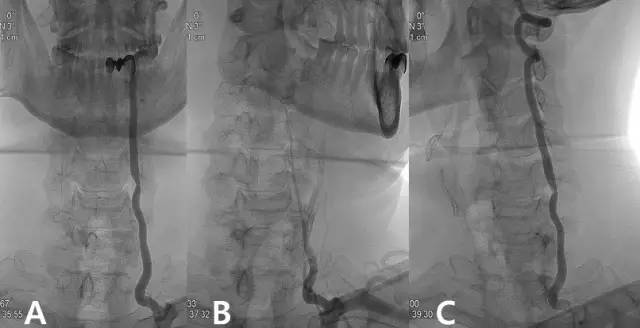

从影像学来看颈椎病为何会引起眩晕